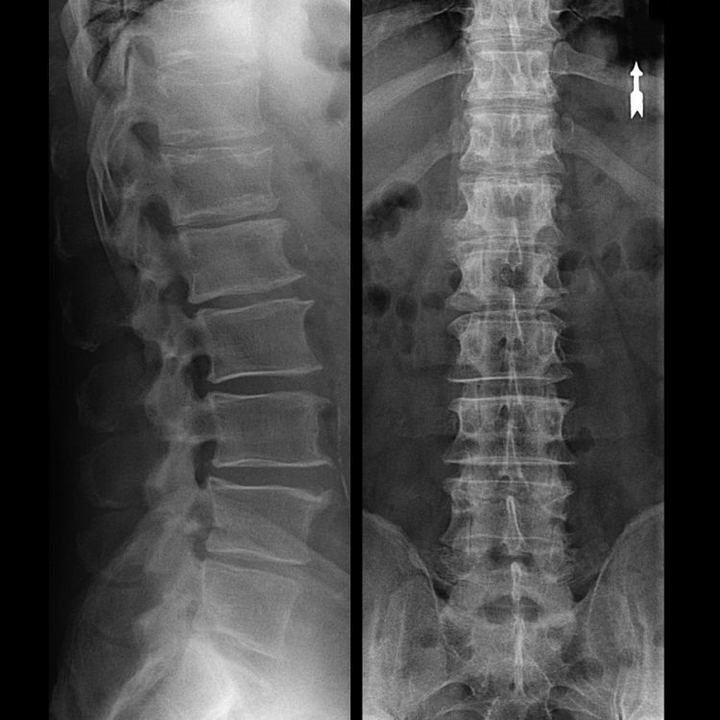

a csigolya régió osteochondrosisa röntgenfelvételen

A nyaki gerinc „röntgenfelvétele”, sőt a hajlítási és nyújtási funkcionális tesztek sem mutatják ki a porcot, mivel a szövetük továbbítja a röntgensugárzást. Ennek ellenére a csigolyák elhelyezkedése alapján általános következtetéseket lehet levonni a csigolyaközi lemezek magasságáról, a nyak fiziológiás görbületének általános kiegyenesedéséről - lordosis, valamint a csigolyákon lévő marginális növekedések jelenlétéről, amelyek felületük hosszan tartó irritációját okozzák a törékeny és dehidratált csigolyaközi lemezek. A funkcionális tesztek megerősíthetik a nyaki gerinc instabilitásának diagnózisát.

Mivel maguk a porckorongok csak CT vagy MRI segítségével láthatók, mágneses rezonancia és röntgen komputertomográfia javasolt a porcok belső szerkezetének és a képződmények, például a kiemelkedések és a sérvek tisztázására. Így ezen módszerek segítségével pontosan felállítják a diagnózist, és a tomográfia eredménye jelzés, sőt aktuális iránymutató az idegsebészeti osztályon fellépő sérv műtéti kezelésére.